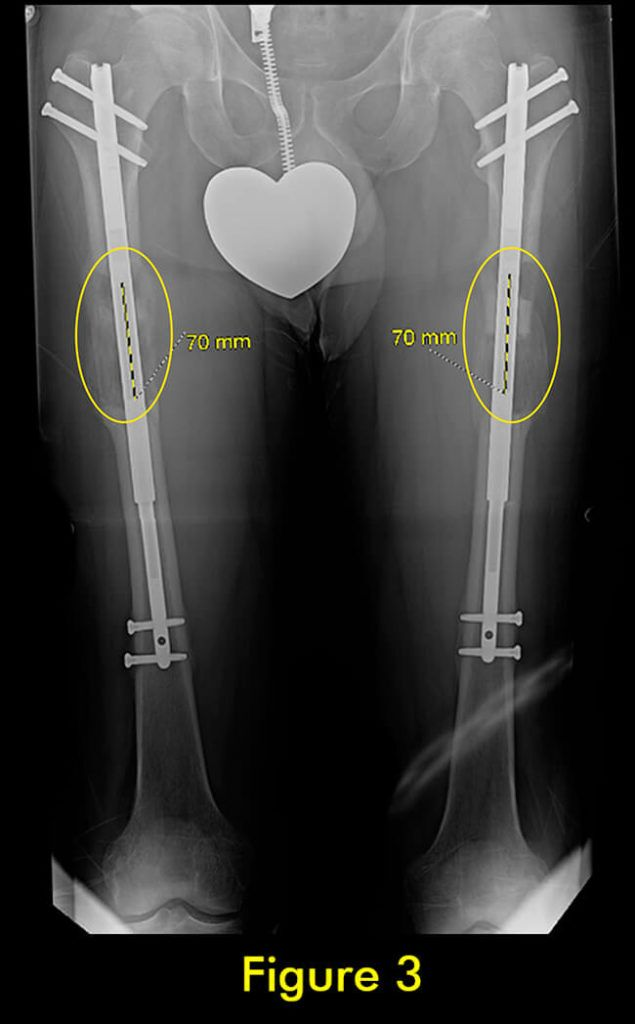

过早合并示意图1

图1:延长量细微差异

过早合并示意图2

图2:X光片确认诊断

过早合并示意图3

图3:重复截骨术

过早合并示意图4

图4:完全巩固